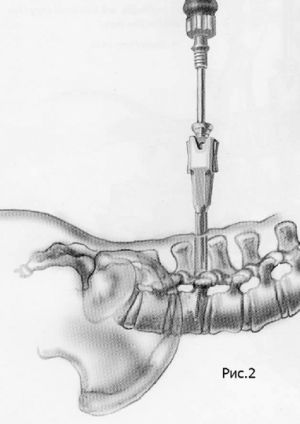

Наиболее современным методом фиксации в настоящий момент является миниинвазивная технология введения винтов через небольшие разрезы. Этот метод позволяет меньше травмировать мышцы разгибатели позвоночника при введении винтов, а также более быстрому выздоровлению пациента и возвращению к обычному образу жизни, активному отдыху и работе. Технология данной фиксации заключается в использовании канюлированных винтов, т.е. винтов с отверстием в центре. В начале в тело позвонка вводится спица, а уже по спице вводится винт. Удаление грыжи диска и введение кейджа в межтеловой промежуток производится через тот же разрез, что и введение винтов.

Рис.7-2. Схема миниинвазивной технологии транспедикулярной фиксации позвоночника. Введение по спице канюлированного винта в сборе с держателем.Рис.2. Схема миниинвазивной технологии транспедикулярной фиксации позвоночника. Введение по спице канюлированного винта в сборе с держателем.